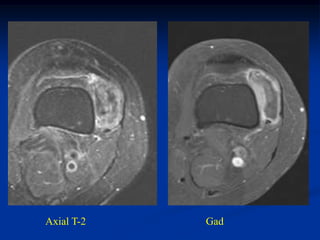

Case #1197

CLASSIC

37 year female with

hibernoma triceps m

Sagittal T-1 MRI

Axial T-1 MRI

Axial T-2 MRI

Axial gad

contrast MRI

Sagittal gad contrast